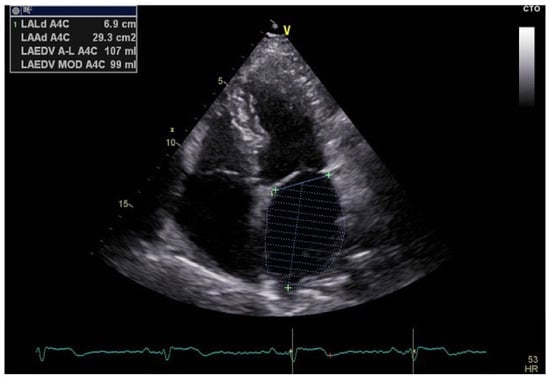

Furthermore, volumetric assessment of the left atrium, such as the left atrial volume index (LAVI), provides additional data on atrial size and remodeling (Figure 5) [28]. Increased LAVI correlates with chronic atrial stress and remodeling [29]. Combining strain, tissue Doppler imaging, and volumetric measurements improves the detection of atrial pathology and aids in risk stratification and severity assessment.

Figure 5.

Apical 4-chamber view obtained through transthoracic echocardiography demonstrating left atrial volume assessment using the biplane area–length method.